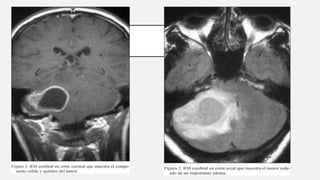

La presencia de un tumor cerebral puede ser revelada con eficacia a través

de la TAC y la REM.

El uso de un medio de contraste (yodo en el caso de TC, en el caso de RM

gadolinio), permite obtener información sobre la vascularización y sobre la

integridad de la barrera hematoencefalica, una mejor definición del nódulo

tumoral respecto al edema circundante y permite avanzar hipótesis sobre

el grado de malignidad.

DIAGNOSTICO La presencia deun tumor cerebral puede ser revelada con eficacia a través de la TAC y la REM. El uso de un medio de contraste (yodo en el caso de TC, en el caso de RM gadolinio), permite obtener información sobre la vascularización y sobre la integridad de la barrera hematoencefalica, una mejor definición del nódulo tumoral respecto al edema circundante y permite avanzar hipótesis sobre el grado de malignidad. Ballesteros M, Vargas-Carvajal. Secondary effects of the radiotherapy in the treatment of brain neoplasms. 2017. 35 (7); 313-366